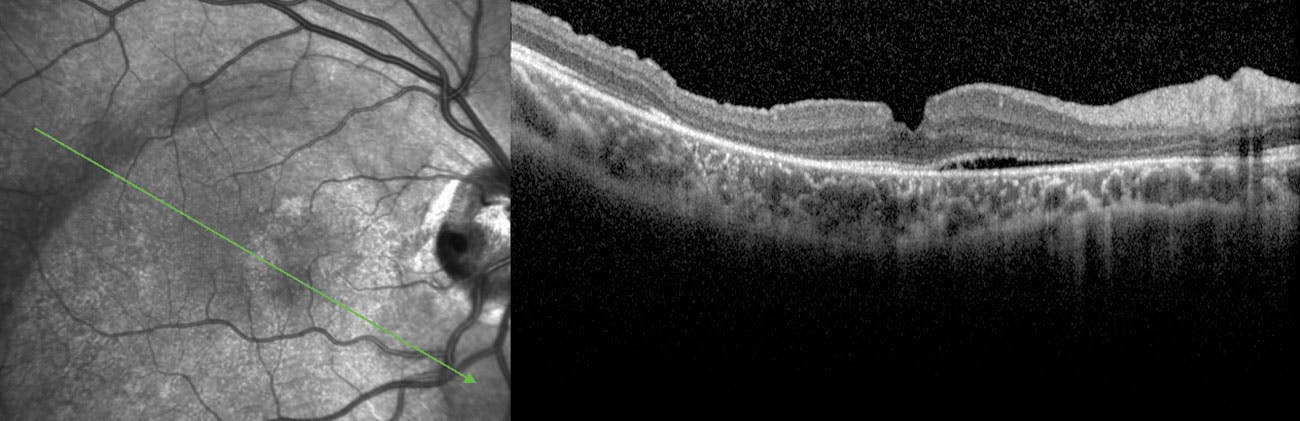

The third case involved a 13-year-old girl with optic disc pit maculopathy and VA of 20/50 OD due to a large macular detachment. We performed PPV and PVD and used a free ILM flap to fill the pit. After fluid-air exchange, we filled the vitreous cavity with 20% SF6 (Video). Three months postoperatively, VA reached 20/25 OD and SRF progressively disappeared over 9 months (Figure). Two years later, visual acuity and macular integrity remained stable.

Figure. SD-OCT B scan of the third patient (13-year-old girl) 9 months after surgery, showing almost complete macular reattachment, except for a line of subretinal fluid.